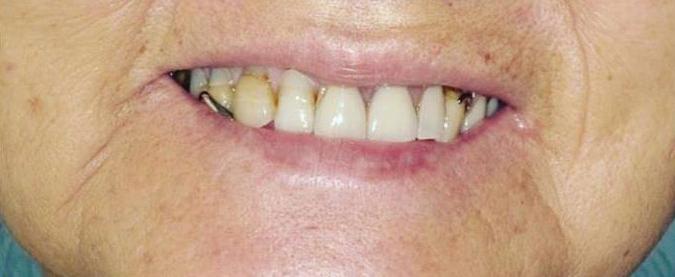

A Reason To Smile Again

Dental Implants

Can just four implants replace all of the teeth on the top or the bottom of your mouth? Thanks to advances in dental implant technology, that answer is a resounding yes.

Believe it or not, tooth loss is extremely common among adults, especially as we age. In fact, more than 35 million people in America are missing

all of their upper and/or lower teeth. Rather than living with the discomfort and hassles of dentures, many people are opting for what is called “all-onfour” dental implant restoration.

All-On-Four: One Full Arch Of Teeth, Four Dental Implants

To fully understand this remarkable technique for replacing teeth, you should first understand what a dental implant is. An implant is a small titanium screw that fits inside your jawbone and replaces the root-part of a missing tooth. Minor surgery is required to insert the implants. Once the implant is in place, a crown is attached to give you a highly realistic-looking and functional prosthetic tooth. Here’s where it gets really interesting: You do not need a dental implant for each and every one of your missing teeth. All you need is four precisely placed implants on the top of your